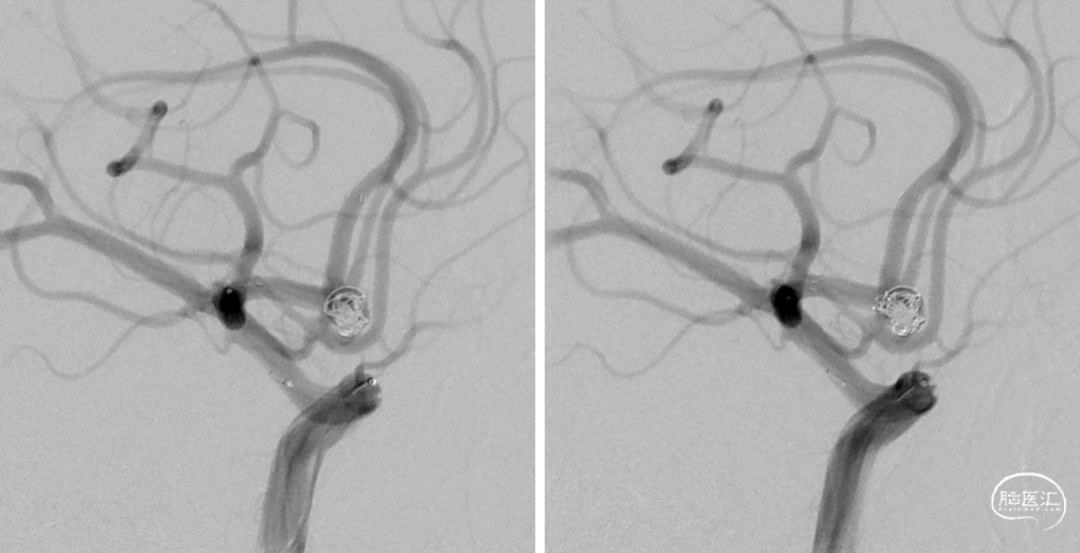

再先后填塞2枚2D 2×6弹簧圈。

见动脉瘤上极还有部分显影,故再上原支架导管SL-10至动脉瘤下极后,填塞1枚2D 2×8软圈。

再填塞1枚1×3、1枚1×2弹簧圈填塞动脉瘤瘤颈。